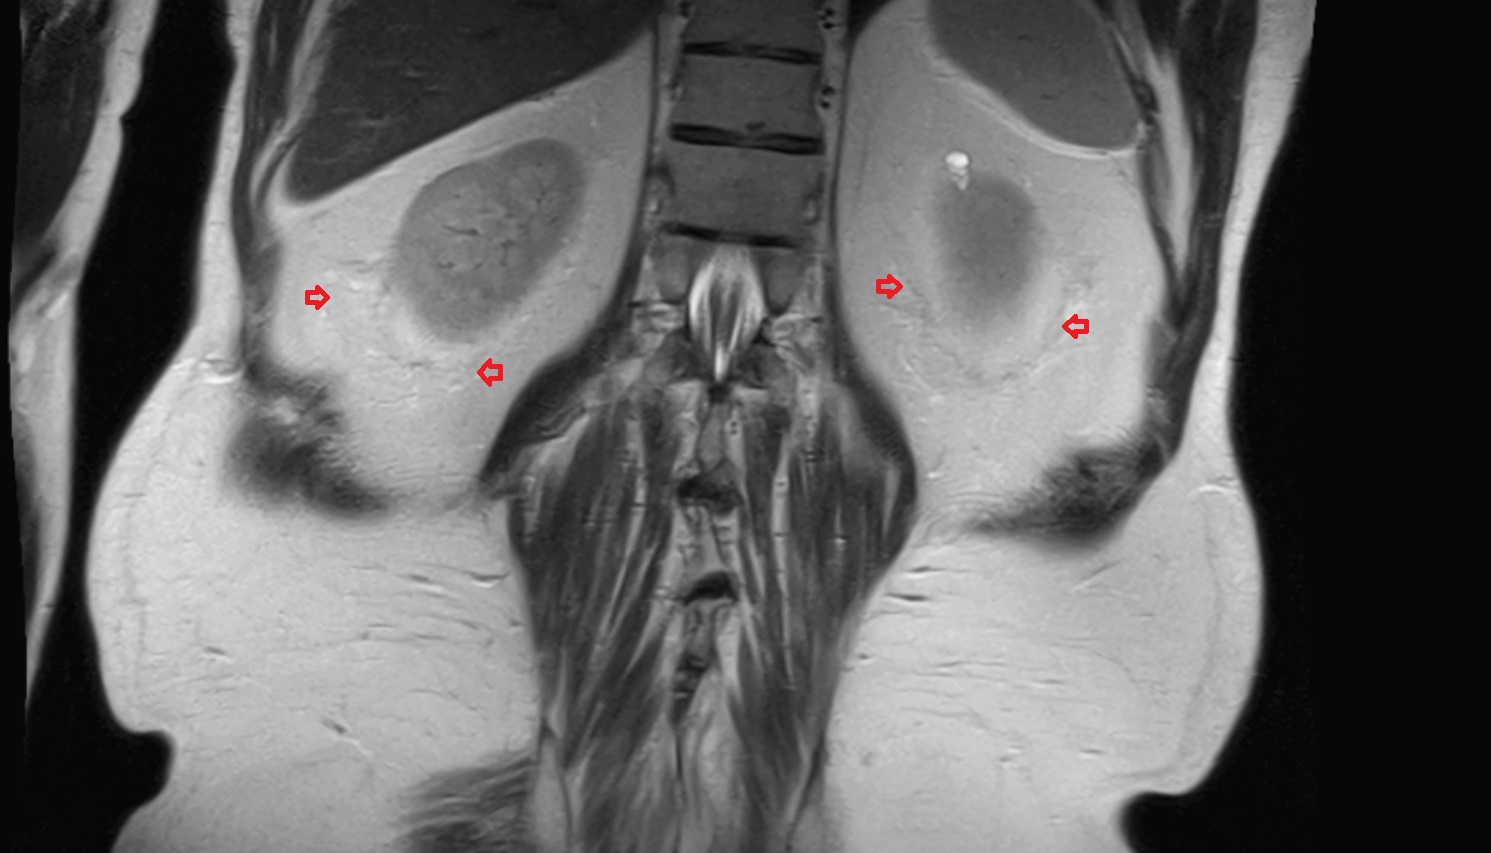

- kidneys

- Right kidney

- Left kidney

- Kidney cortex (Renal cortex)

- Renal capsule

- Renal medulla

- Renal pyramids

- Renal fascia

- Renal artery

- Renal vein